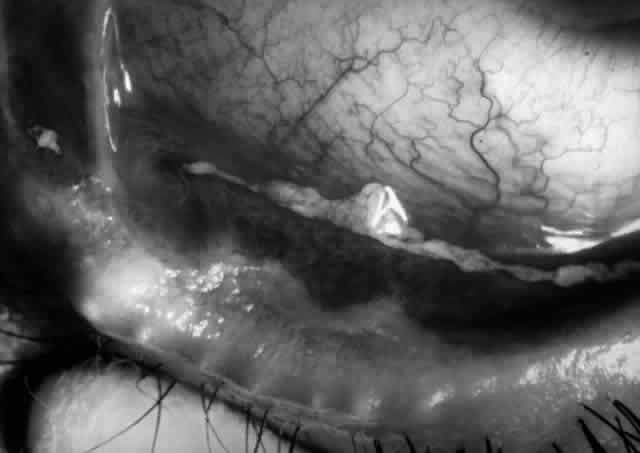

Clinically, the ocular disease in cicatricial pemphigoid (OCP) may present unilaterally in the form of a chronic, recurrent catarrhal conjunctivitis, but it eventually becomes bilateral. Subepithelial fibrosis is characteristic of stage 1 of OCP (Fig. 7). Stage 2 shows fornix foreshortening (Fig. 8), and symblepharon formation is the hallmark of stage 3 (Fig. 9). Stage 4, end-stage disease, is characterized by ankyloblepharon and surface keratinization (Fig. 10). Obstruction of the lacrimal ductules and meibomian gland ducts eventually produces an unstable tear film and progressive sicca syndrome, but it is to be emphasized that OCP is not a dry-eye syndrome until late in the disease course.20 Trichiasis and entropion occur because of the subepithelial fibrosis, with eventual keratopathy, corneal neovascularization, and corneal ulceration and scarring.20

Fig. 7. Stage 1 cicatricial pemphigoid, with cicatrizing conjunctivitis, and fine striae-type areas of subepithelial fibrosis, but without evidence of shrinkage of the conjunctiva.